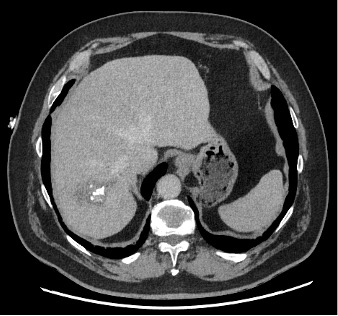

Ce CT-scanner, initialement réalisé chez une patiente de 70 ans à la recherche d’une dissection aortique scanner, met fortuitement en évidence une lésion hépatique.

Les douleurs de la patiente ont bien évolué sous traitement symptomatique. Son bilan sanguin avec FSS, CRP, tests hépatiques et pancréatique est dans la norme. Au vu de la présence de lésions kystiques hépatiques présentant des calcifications et des zones de nécrose sur le scanner, une sérologie pour l’échinococcose alvéolaire (EA) est demandée.

Le diagnostic de la maladie se base sur l’imagerie et la sérologie. L’US hépatique ainsi que le CT-scanner ou l’IRM peuvent être utilisés, mais les deux derniers permettent d’évaluer l’extension de la maladie. En cas de lésions calcifiées, le PET/CT au FDG permet de déterminer le degré d’activité métabolique de la lésion.